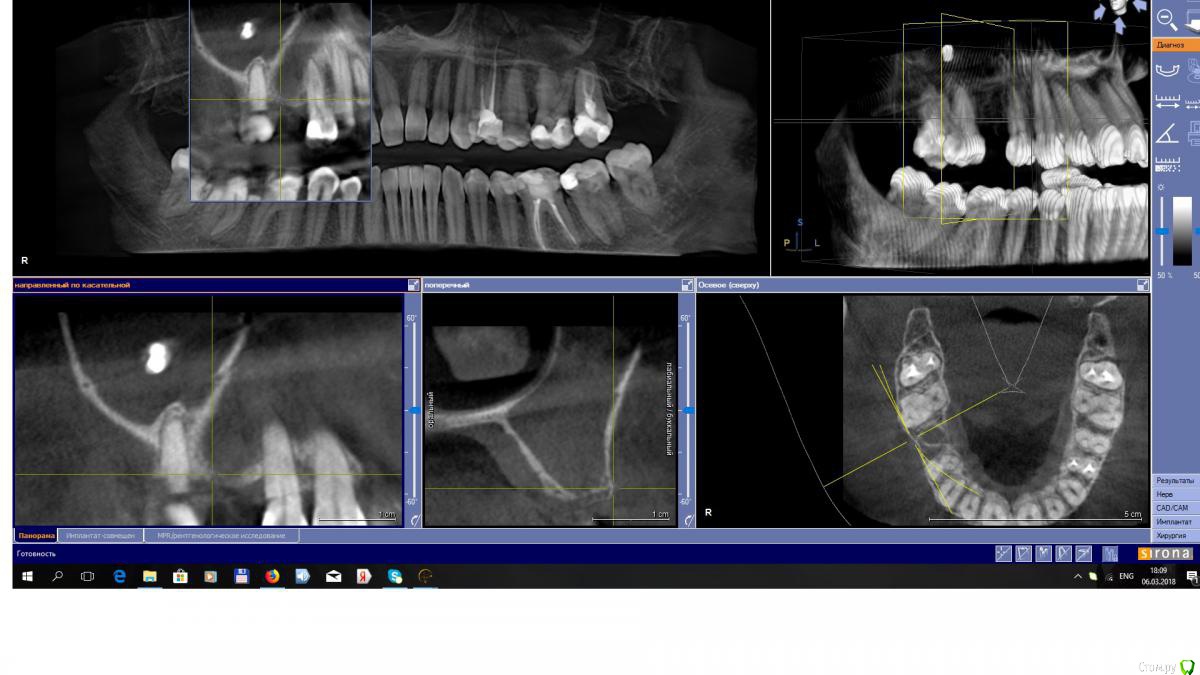

Zubnik86rus Опубликовано 8 марта, 2018 Поделиться Опубликовано 8 марта, 2018 Незнаю как вставить картинку, но 6ка видно полость кариозную сообщающующуюся с полостью зуба и дистальный щечный корень в пазухе, имхо вот и виновник такой слизистой Ссылка на комментарий

TIGER Опубликовано 10 марта, 2018 Поделиться Опубликовано 10 марта, 2018 Это грибы...К ЛОРу отправляйте 1 Ссылка на комментарий

Bier Опубликовано 12 марта, 2018 Поделиться Опубликовано 12 марта, 2018 про грибы согласен. Ссылка на комментарий

Irouil Опубликовано 14 марта, 2018 Поделиться Опубликовано 14 марта, 2018 Не до конца грибковое тело если убрать то дальше скобли-не скобли... Ссылка на комментарий